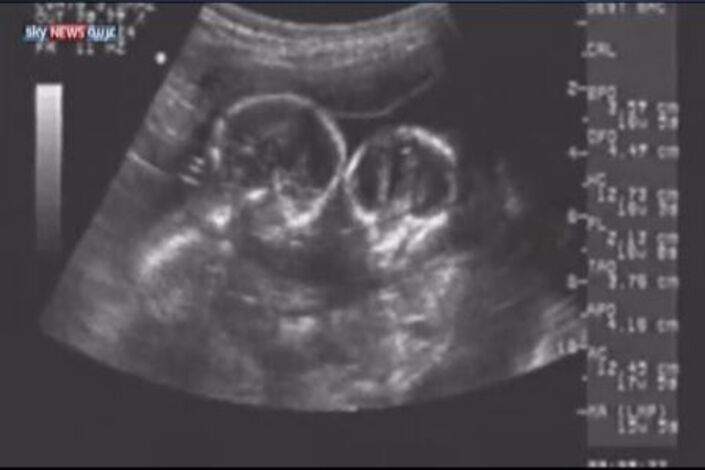

لطالما ثارت تساؤلات بشأن إمكانية صيام السيدات الحوامل، خصوصا أن الحمل يحتاج إلى مقومات عديدة، ليكون آمنا وصحيا، مثل الغذاء السليم وكثرة شرب السوائل والراحة التامة.

وبينما تتوالى الأسئلة بشأن الحمل والصيام في شهر رمضان، تتنوع الإجابات طبقا لكل حالة، فمن حيث المبدأ لا يؤثر الصوم على الحامل في المرحلة الثانية من الحمل أي بعد مرور 4 أشهر منه.

وفيما يتعلق بصحة الجنين فإن بعض الدراسات تشير إلى تأثيرات طفيفة على المواليد الجدد جراء صوم الأمهات، وهذه التأثيرات قد تذهب تدريجيا عند نمو الطفل.